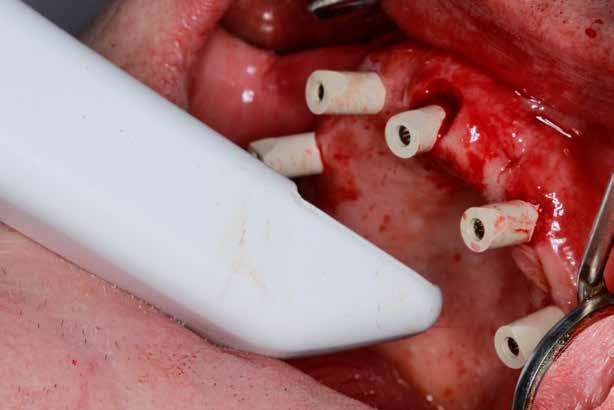

Az implantológiában inkább a szájsebészeti jellegű témák voltak hangsúlyosak, a manuális eljárások dominanciája volt jellemző. Ma inkább a különleges csontpótlásokról, az előre megtervezett fogpótlásból (backwards planning = visszafelé tervezés) kiindult sebészeti tervezésről esik sok szó, ez vált követelménnyé. A digitális eljárások fölénybe kerültek a manuálisokkal szemben. A régi technológiák folyamatosan kikopnak a gyakorlatból. És itt is kérdés: Mi az, ami megfelel – még vagy már – a szakma szabályainak? Már csak emiatt is sok mindent újra kell gondolni (4–5. képek)